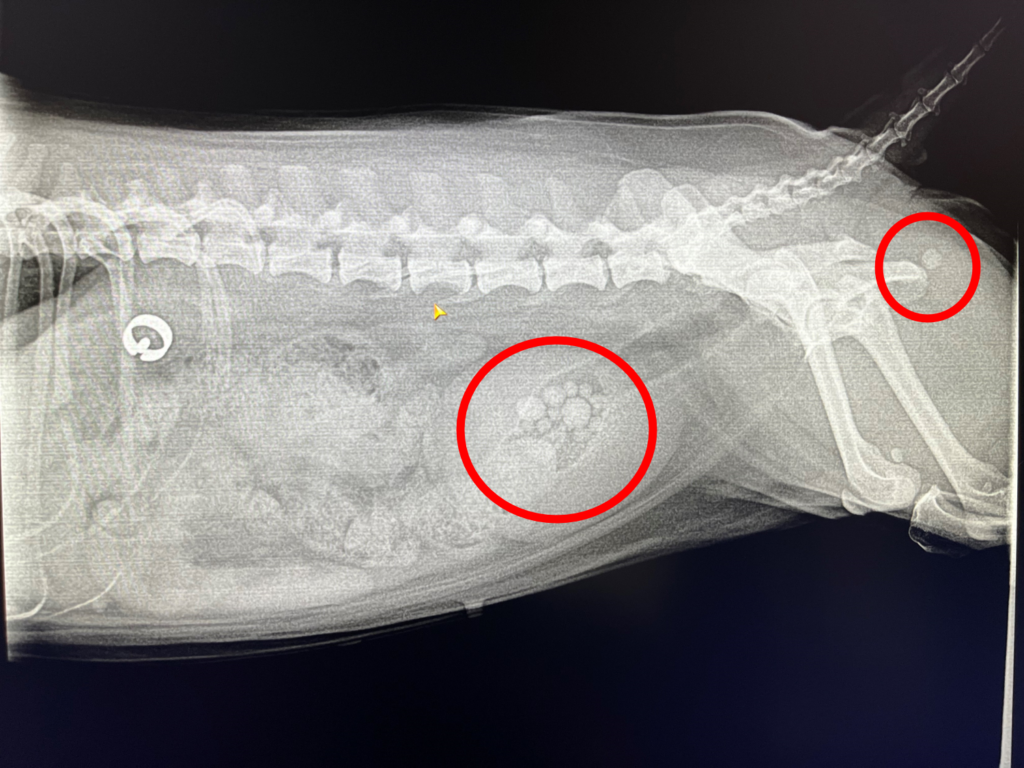

これは先日膀胱結石の手術を受けた子から摘出した膀胱結石です。

大きなものが尿道に詰まり、おしっこが出なくなったため、体調が悪くなったことで見つかりました。

この白く丸く映っているのが膀胱結石です。

結石があると尿道を詰まらせる恐れがあるだけでなく、膀胱炎や膀胱の出血を引きおこす原因にもなります。